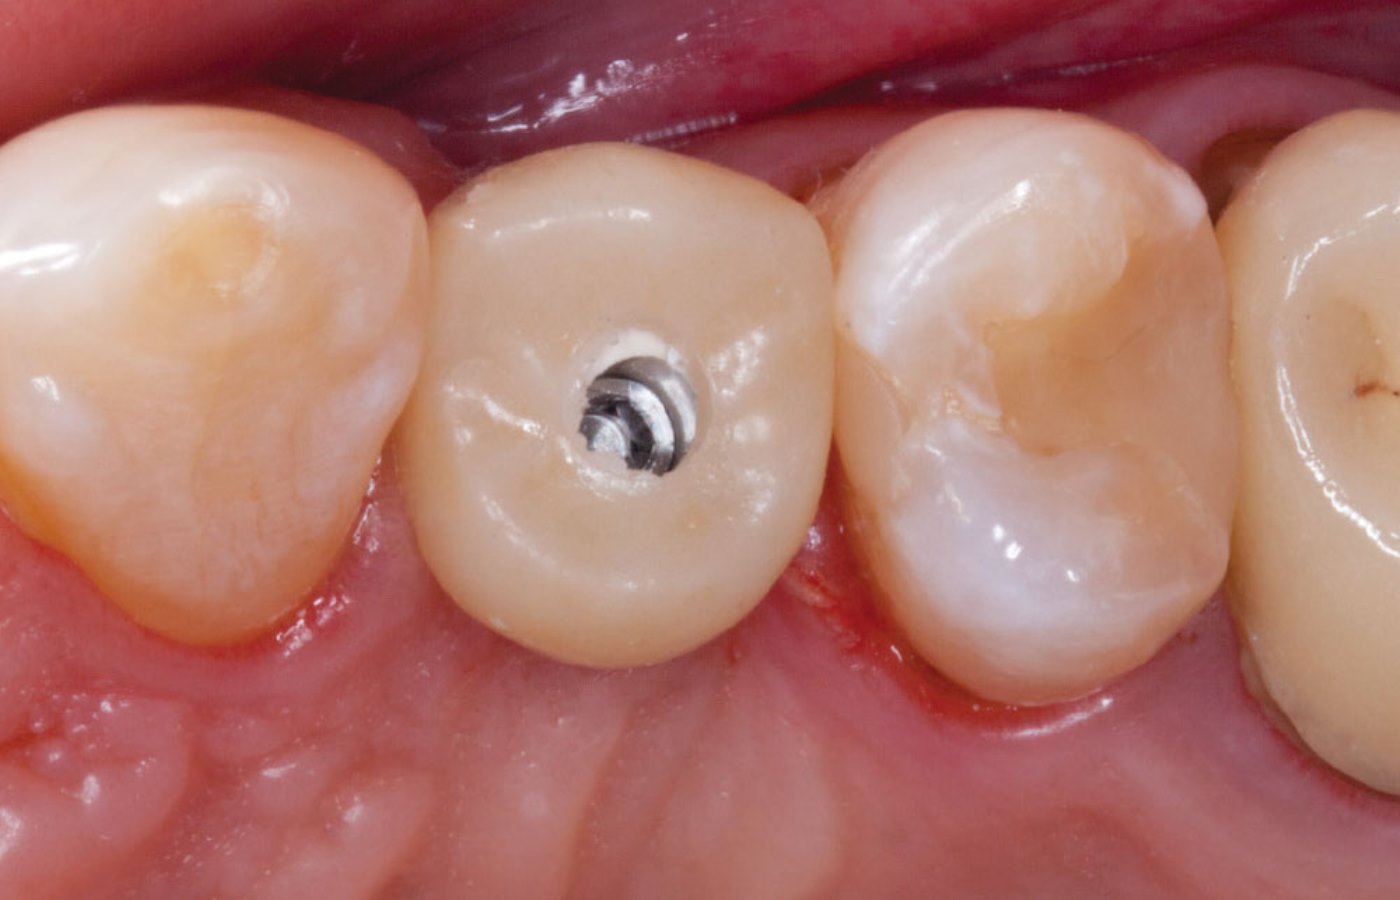

عکس دندان خراب. عکس دندان عصای دست دندان پزشک به هر شکل که عکس گرفته شود تصویر حاصل به دندان پزشک شما در تعیین اقدام مناسب کمک شایانی خواهد کرد. عکس سمت راست دندان با مینای خراب و عکس سمت چپ دندان سالم می باشد. مسواک زدن بهداشت دهان و دندان جویدن ناخن دندان قروچه درمان دندان. سلامت و بهداشت بیماری ها و راه درمان22 عادتی که دندان ها را خراب.

مهم ترین کار یک معاینه ی کامل است این معاینه شامل نگاه سطحی بر دندان های شما گرفتن عکس با استفاده از اشعه x از آنها و ساختن مدل پلاستیکی از دندانهای شما میشود سپس تیم دندانپزشکی یا. عکس بیت کوین به زودی وارد مبادلات مالی می شود. تشخیص پوسیدگی دندان ها از روی عکس های رادیو گرافی کاری است که نیاز به علم مربوطه دارد.